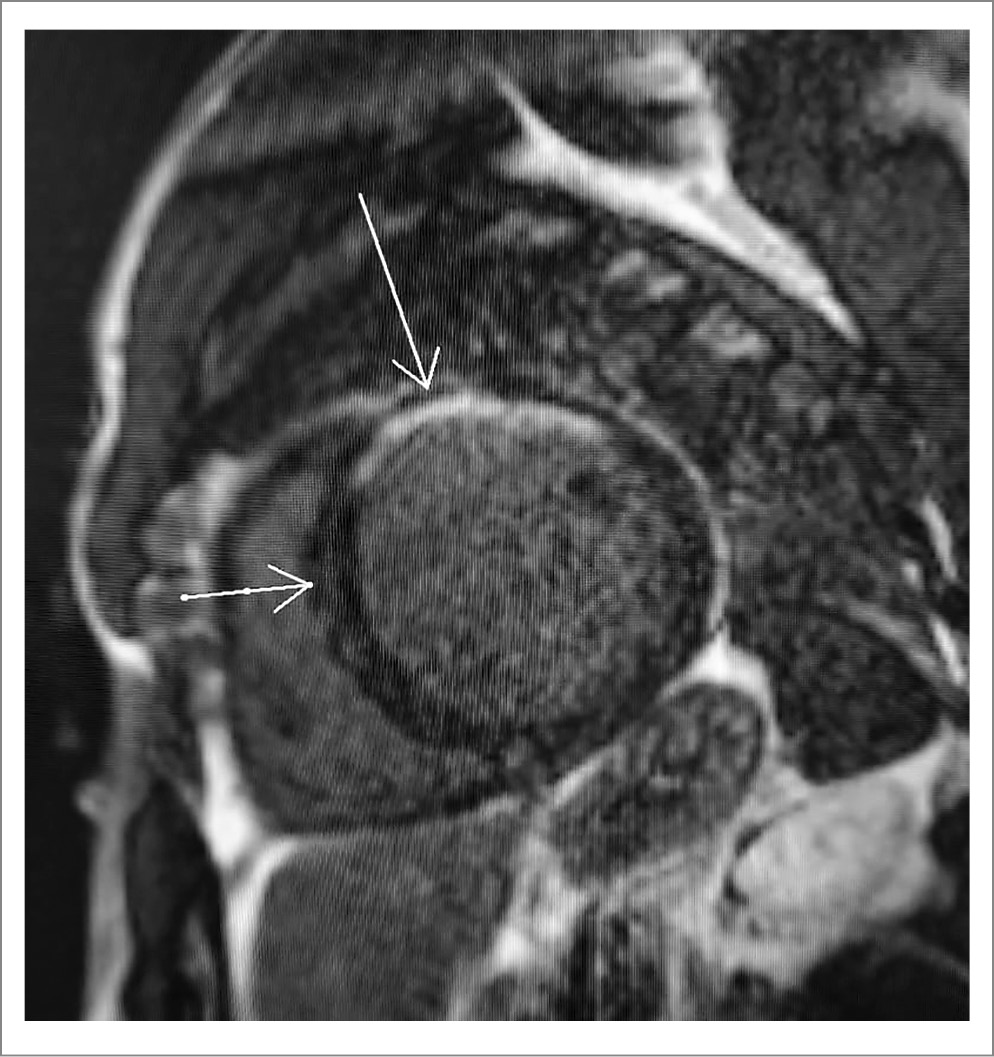

Пациенту выполнена магнитно-резонансная томография (МРТ) сердца с внутривенным контрастированием, по данным которой ФВ ЛЖ составляла 14%, сократимость ЛЖ была снижена диффузно. Межжелудочковая перегородка (МЖП) в базальном и среднем сегментах равнялась 12–13 мм, толщина остальных стенок ЛЖ – 9–10 мм. Наблюдалось 2 типа накопления контраста в миокарде ЛЖ: интрамиокардиальное линейной формы в базальном и среднем сегментах по типу «стрии» и трансмуральное в передней стенке среднего сегмента, передней стенке и передних отделах боковой стенки апикального сегмента (рис. 3).

Рис. 3. МРТ пациента

По результатам МРТ у нашего пациента выявлено 2 типа накопления контраста в миокарде ЛЖ: интрамиокардиальное в МЖП (наиболее характерное для КМП) и трансмуральное (ишемическое). Ассоциированный с приемом ААС фиброз миокарда описан по данным аутопсии [18]. Как и в нашем случае, секционные данные говорили о преимущественном интрамиокардиальном фиброзе в области МЖП [18, 19]. Поскольку миокардиальный фиброз вносит важный вклад в развитие аритмогенного субстрата и клинически значимых нарушений ритма [20], нашему пациенту рекомендована установка ИКД без предшествующего 3-месячного курса оптимальной медикаментозной терапии.